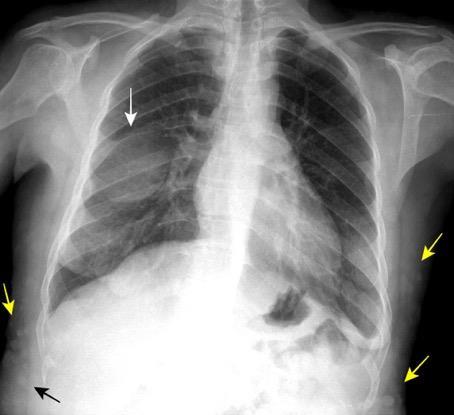

1/30.000 nacimientos

Hipoplasia/ausencia de mama o pezón.

Hipoplasia de tejidos subcutáneos.

Ausencia de la porción costoesternal del pectoral mayor.

Ausencia del pectoral menor.

Ausencia de cartílagos costales o costillas, 2,3 y 4.

Variante: Síndrome de Poland con dextrocardia.

Hipoplasia Art. pulmonar dcha. Atelectasia.

Bansal A, et al. Poland syndrome: a case report. BMJ Case Rep 2017

Mutlu H et al. A variant of Poland syndrome associated with dextroposition. J. Thorac. Imaging. 2007